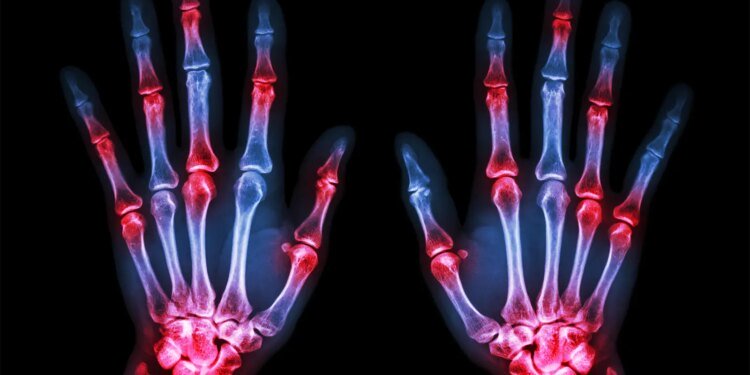

- The Sharp/van der Heijde (SvdH) method for analyzing X-ray images is the standard way to measure joint space narrowing and bone erosions in rheumatoid arthritis, requiring well-trained readers.

A machine-learning system for analyzing rheumatoid arthritis (RA) patients’ X-rays was able to produce Sharp/van der Heijde (SvdH) scores, the standard way to quantify joint space narrowing and bone erosions, with good accuracy when compared with human readers, researchers said.